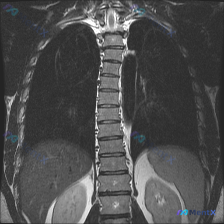

这张胸部MRI的胸椎序列真的正常吗?一眼看过去好像哪里不对

最初看这份胸部MRI冠状位T2加权像的分析,结论是「无明显病灶、解剖结构正常」。

但问题里特意加了一个词「Scoliosis(脊柱侧弯)」,再回头看图像——好像胸椎的序列确实不是一条直线?

如果只看这份初始描述:「胸椎序列连续、椎体骨髓信号中等、椎间盘未见明显信号异常、骨皮质连续」,你会不会觉得完全正常?